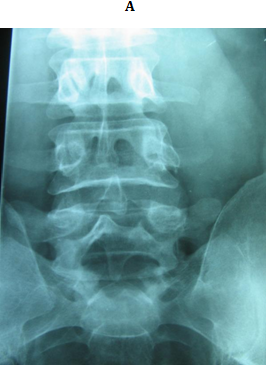

Figure 3 18 years old male with bilateral pars defect at L5 underwent the procedure. (A) Preoperative lateral plain radiograph showing the defect (B) Preoperative MRI shows intact intervening disc (C, D) Immediately postoperative plain radiographs (E) CT 1 month later. Note the bone graft incorporating at the defect site.

Figure 4 A 23 years old female with double level spodylolyis at L4 and L5. (A, B) Preoperative plain radiographs. (C,D) 3 months after direct pars repair with cable screw construct at both levels.